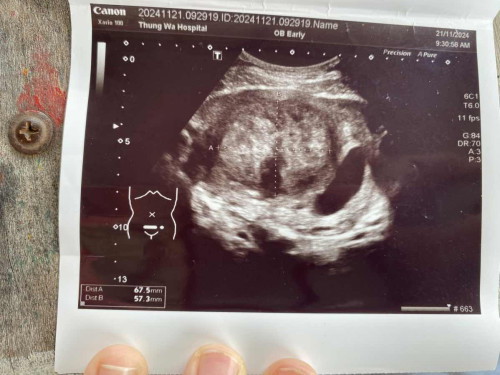

มีเนื้องอก ขณะตั้งครรภ์

สวัสดีค่ะ คือว่าเราไปอัลตร้าซาวด์ครั้งแรกมาแล้วเจอก้อนเนื้ออันนี้ยาว8เซนติเมตรและหนา5เซน เราเครียดมากค่ะ เพราะมันไปเบียดพื้นที่ของลูกเรา เอ็นดูลูกมากค่ะ หมอบอกมันเป็นเนื้องอก แต่ก็ไม่รู้ว่ามันจะโตอีกมั้ย เค้าต้องส่งตัวไปอีก โรงพยาบาลนึงเพราะไม่มีหมอเฉพาะทาง สงสารลูกมากค่ะ#ท้องแรก #ขอความคิดเห็นของคุณแม่หน่อยค่ะ #ขอบคุณล่วงหน้าสำหรับความคิดเห็นค่ะ